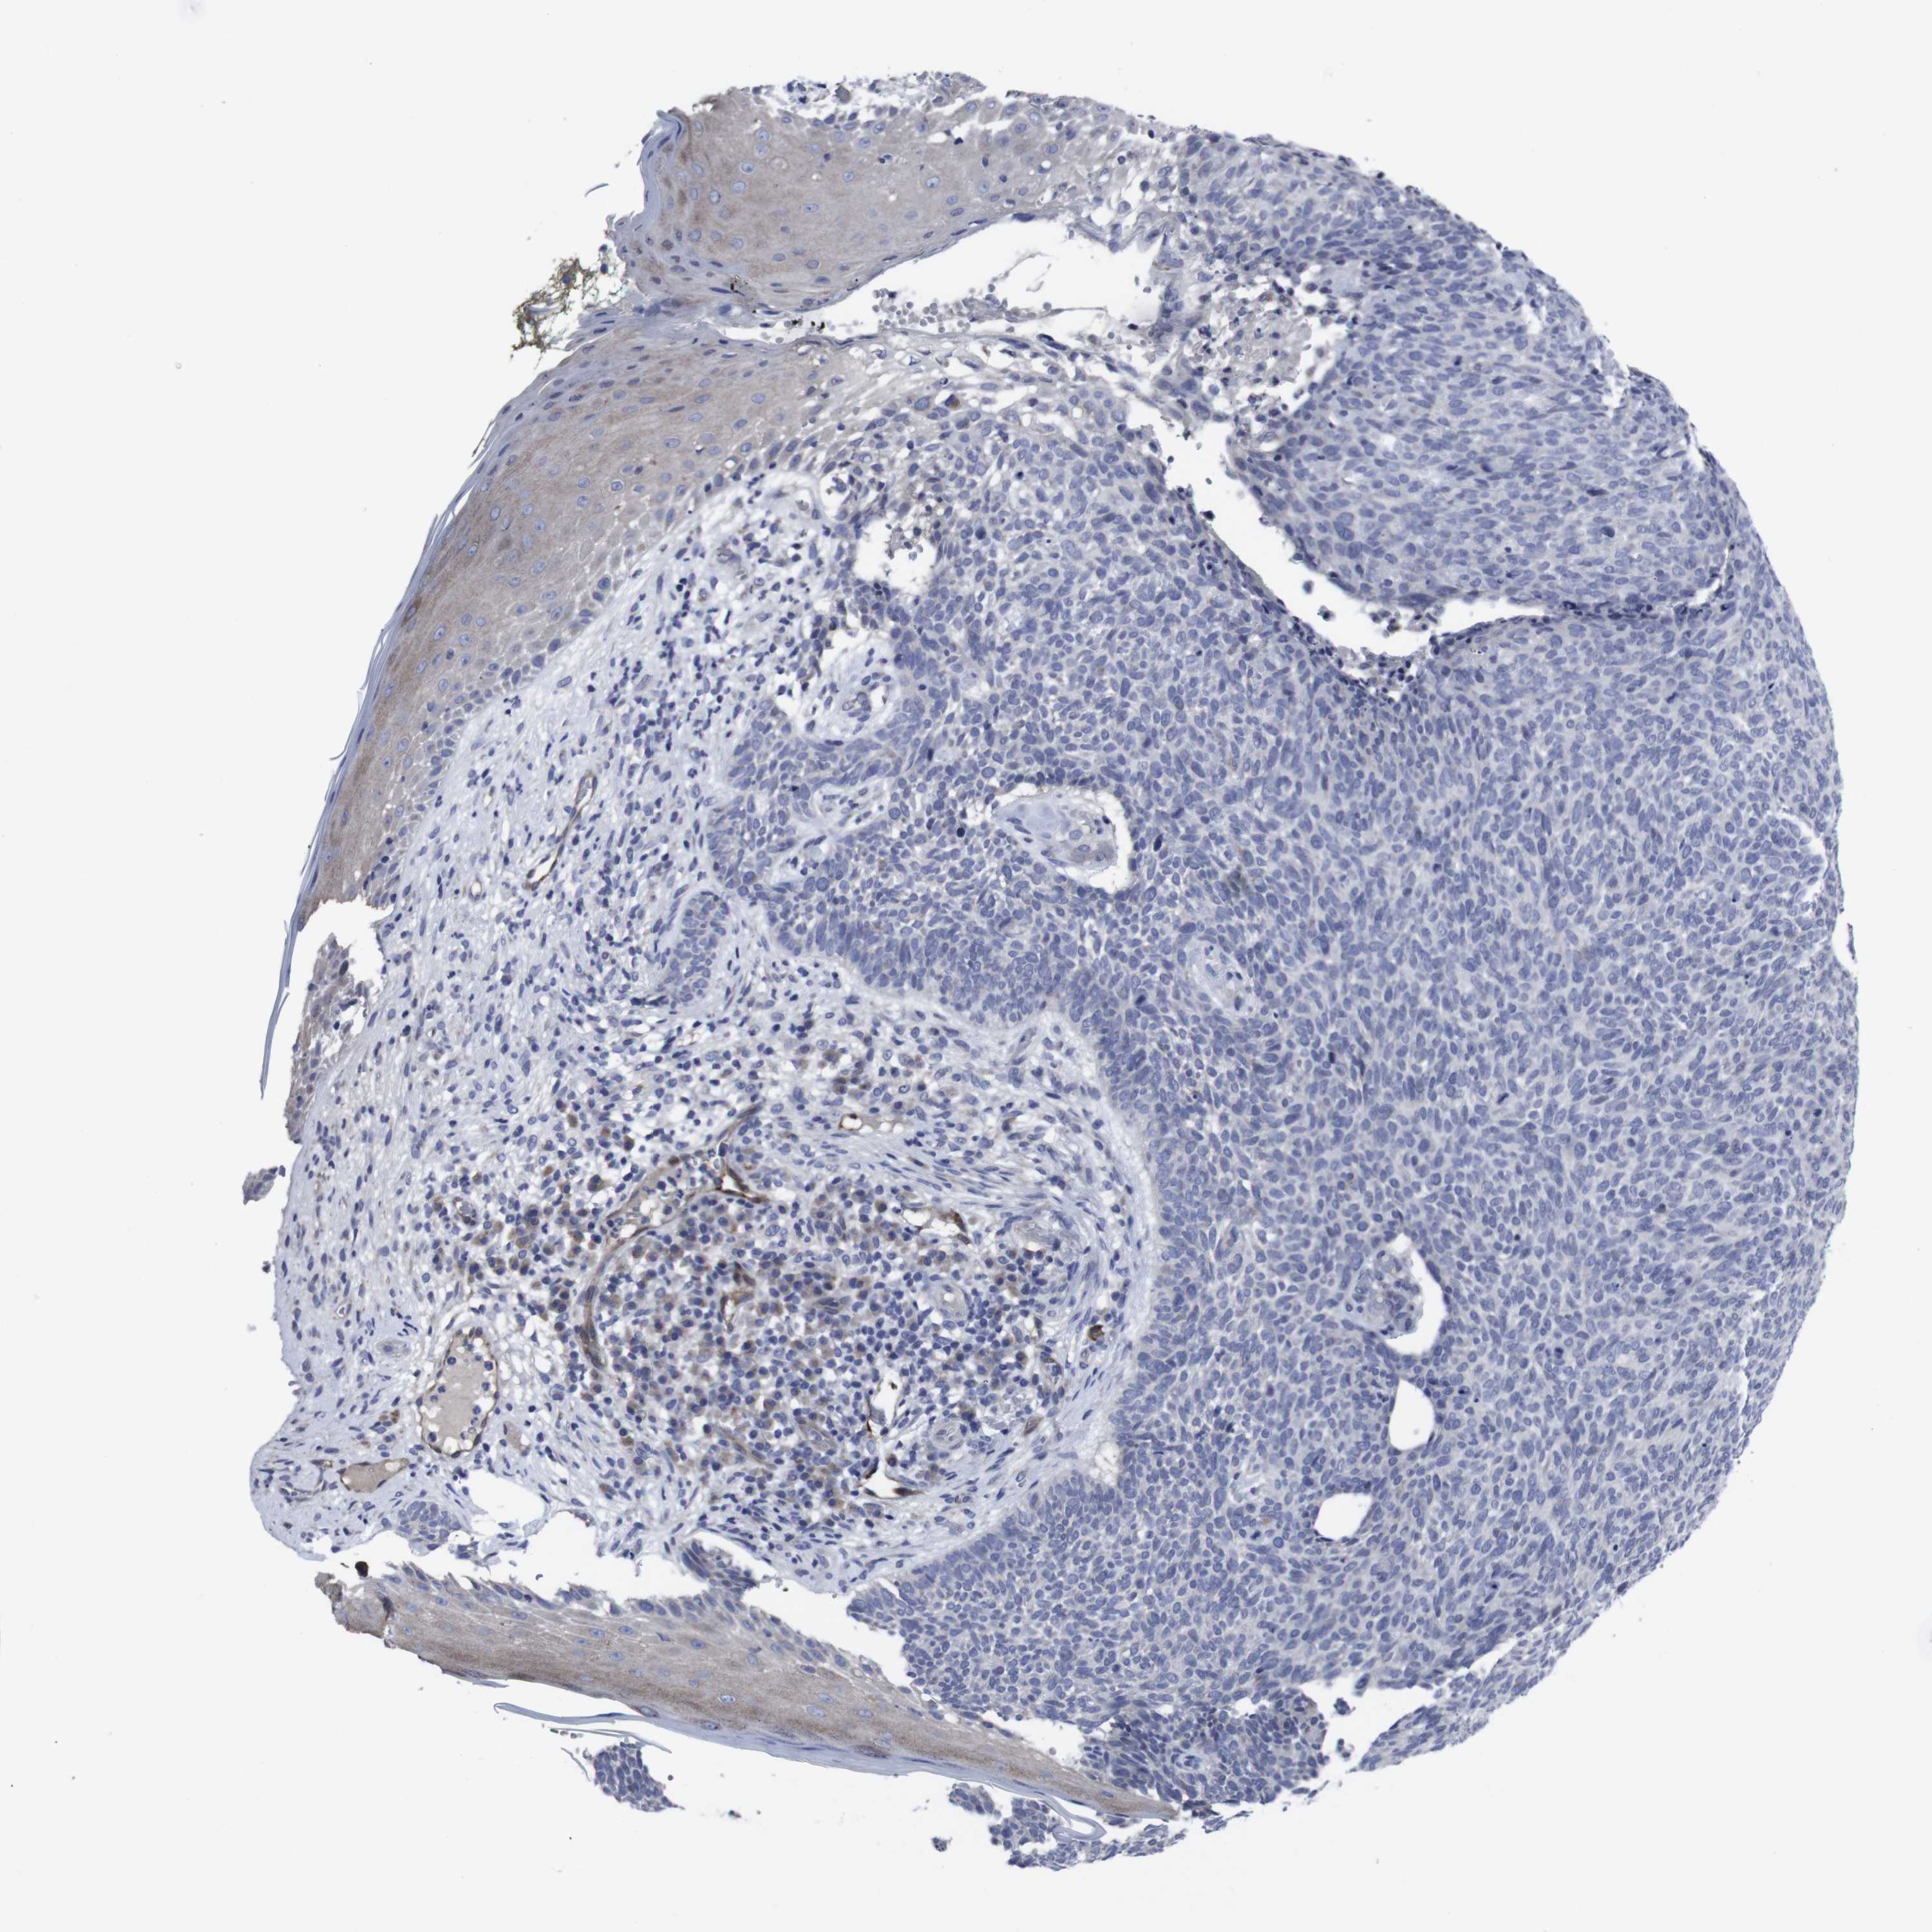

SKIN CANCER - Protein expressioni

A mouse-over function shows sample information and annotation data. Click on an image to view it in a full screen mode. Samples can be filtered based on level of antibody staining by selecting one or several of the following categories: high, medium, low and not detected. The assay and annotation is described here.

Each image is clickable and will lead to virtual microscopy that enables deeper exploration of all samples and also displays staining intensity scores, fraction scores and subcellular localization as well as patient and tissue information for each sample.

Antibody CAB040581

Squamous cell carcinoma, NOS